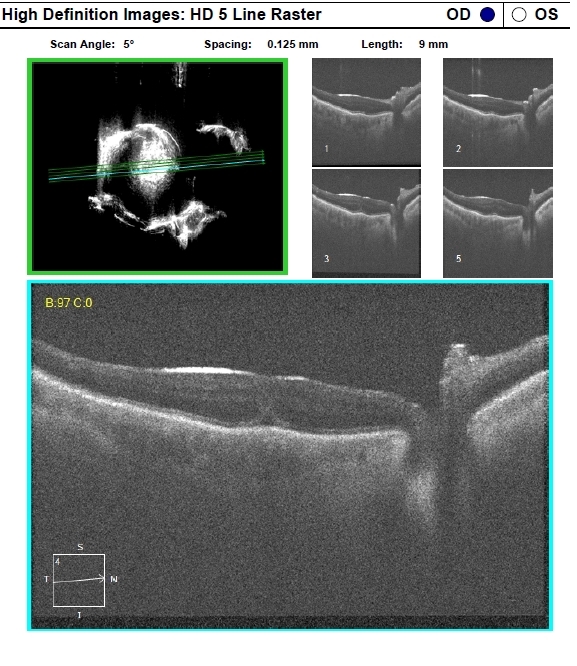

- full thickness macular hole, optical coherence tomography (OCT)

- POD 1 - hole closed as seen on OCT